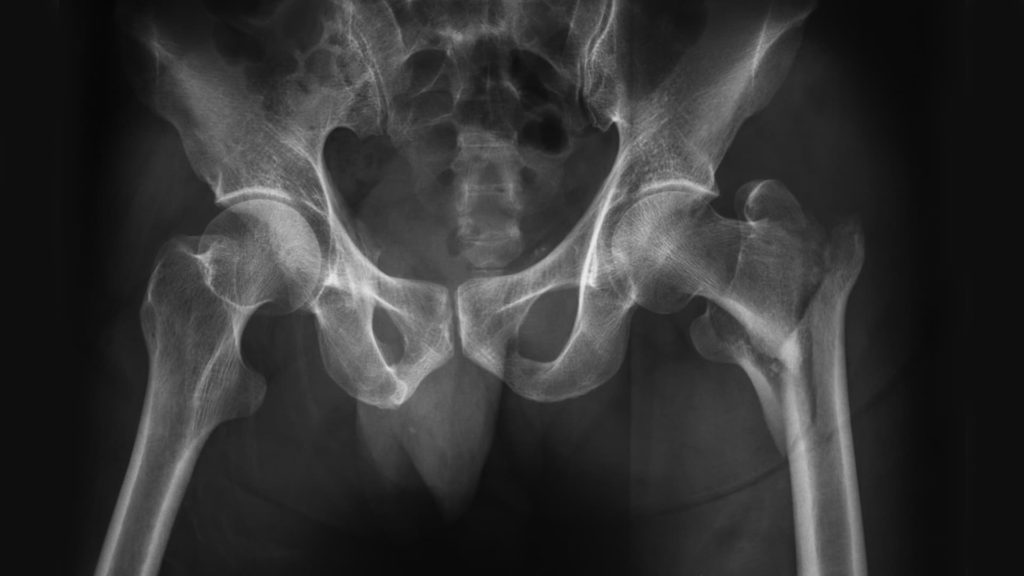

Source: scaleappfdt.pages.dev Children's Fracture Treatment and Correction Kids Orthopedic , Cet enclouage permet de reprendre l'appui plus tôt, vers 3 ou 4 semaines après l'intervention. Femur fractures are classified depending on: Location of fracture on the bone (top, middle, bottom)

Figure 3 from Fractures de la diaphyse fémorale chez l'enfant Semantic Scholar . Il peut tomber de la table à langer ou de son lit à barreaux en tentant de l'escalader Femur fractures are classified depending on: Location of fracture on the bone (top, middle, bottom)